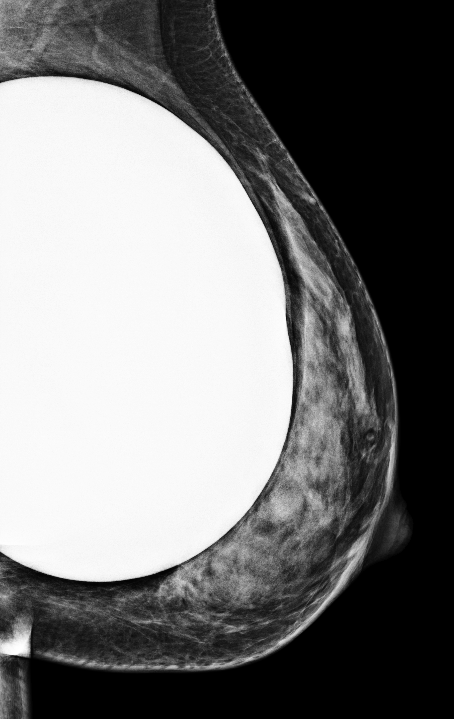

Having breast implants does not increase your risk of breast cancer.

However, the implants can make it more difficult to perform a mammogram, especially if a technologist doesn't see women with implants on a regular basis. The implant can obstruct views during the imaging process and it takes an experienced radiology team to get all the right angles to get you the most accurate results.

Cancer centers are familiar with performing imaging on women who have implants, especially those who have undergone breast reconstruction as part of a treatment plan and continue to get regular imaging throughout their lifetime.

Breast mammogram with an implant.